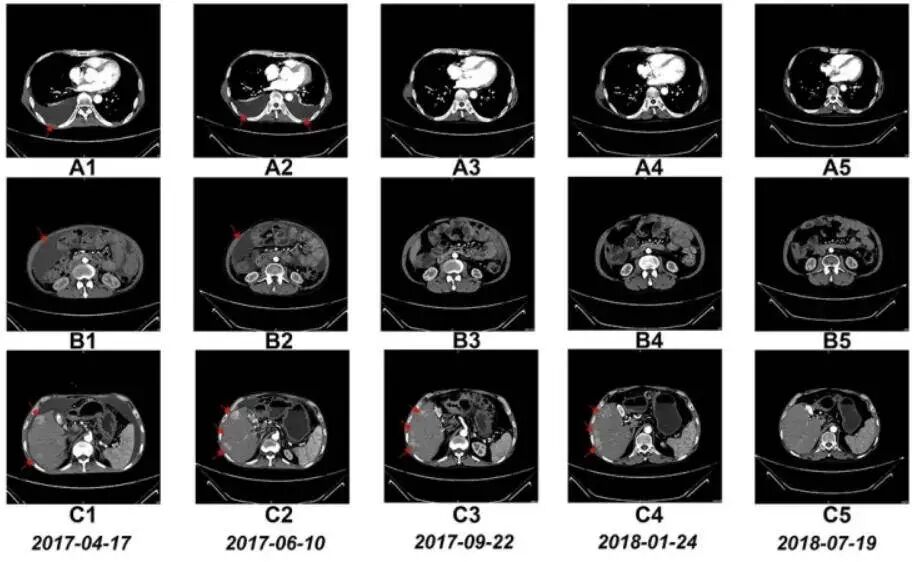

随着年龄的增长,癌症的发病率逐渐上升,中老年人成为癌症的高危群体。这背后,既有衰老导致的免疫系统功能衰退,使得NK细胞的活性与数量大打折扣,难以高效地识别和清除体内突变的癌细胞;也有长期不良生活环境的影响,如长期接触化学污染物、辐射,或是有抽烟、酗酒等不良嗜好,这些都会使身体细胞长期遭受损伤,基因更容易发生突变,从而诱发癌症。对于这类人群,补充NK细胞就如同为免疫系统“增兵”,能够显著增强其对癌细胞的监控与杀伤能力。NK细胞能够直接杀伤肿瘤细胞,同时释放细胞因子诱导细胞凋亡,从源头上遏制癌症的发生和发展。通过回输NK细胞,我们可以为身体注入新的活力,让免疫系统在癌症萌芽之初便将其扼杀,从而降低患癌风险。2016年6月,一名晚期肝癌患者在接受每月一次的NK细胞输注治疗后,成功带瘤生存超过四年。 NK细胞治疗前和治疗期间的CT扫描结果有些人似乎总是被各种病菌“盯上”,频繁感冒、呼吸道感染不断,伤口愈合也慢吞吞,这是免疫力低下的表现。无论是先天性免疫缺陷,还是后天因过度劳累、营养不良、长期熬夜等因素导致的免疫系统“疲软”,都会使NK细胞的功能无法正常施展。补充NK细胞对于这类人群来说,能够快速激活机体免疫应答,增强其对外来病原体的抵御力。NK细胞在人体内游走迅速,一天24小时可以循环数百圈,堪称细胞界的“劳模”。它们能够直接清除体内的病毒、细菌等病原体,同时全面激活其他免疫细胞共同作战,帮助身体迅速从感染中恢复,重建健康防线。研究显示,通过从人体内提取NK细胞,在实验室中进行“培养”和“扩增”,再将这些增强后的NK细胞输回体内,就像是给NK细胞开了一个超级训练营,让它们更加强大,数量也更多。慢性炎症就像身体里的一场“小火苗”,经久不灭,如慢性肝炎、肠炎、盆腔炎等。这些炎症环境不仅持续损伤组织器官,还会干扰免疫系统的正常调节。NK细胞在慢性炎症中常常陷入“疲惫”状态,数量减少、活性降低。相关研究表明,大概有六分之一的癌症是因为炎症引起的。比如,乙肝患者的肝组织会因为炎症而留下疤痕,这个过程会大大增加患肝癌的概率。其他一些慢性炎症,如胃溃疡以及溃疡性结肠炎,也会增加患胃癌以及结肠癌的概率。此时引入NK细胞,它们能够发挥强大的调节作用。NK细胞能够调节炎症因子的分泌,减轻炎症反应,同时靶向清除因炎症引发的病变细胞。这种双重作用机制使得NK细胞在慢性炎症的治疗中展现出独特的优势。通过回输NK细胞,我们可以帮助身体摆脱慢性炎症的纠缠,防止病情进一步恶化,为组织修复创造良好条件。现代社会高强度的工作节奏、巨大的精神压力让上班族们长期处于亚健康状态。身体疲劳、精神萎靡、睡眠不佳成为常态。长此以往,免疫系统也跟着“拉响警报”,NK细胞的活力受阻,使得身体对疾病的易感性大增。补充NK细胞对于这类人群来说,恰似一场及时雨。NK细胞能够迅速恢复其正常活性,提升整体免疫力。它们不仅能够直接清除体内的衰老细胞、病变细胞,还能通过释放细胞因子等机制调节免疫系统的平衡。通过回输NK细胞,上班族们可以重拾精力充沛的状态,从容应对工作与生活的挑战。央视曾报道过一则案例,一名女性企业家经常感到自己力不从心,不仅莫名其妙地腰酸背痛、食欲低下、失眠多梦等亚健康情况频频出现,而且疲劳状态也越来越难以缓解。以前早睡晚起补一觉就可以恢复体力,现在连入睡都困难。儿子带她去做了全身检查,发现各项指标都属正常范围,这就纳了闷了,她的身体到底出了什么问题?据世界卫生组织统计,全世界有75%的人处于亚健康状态,而长期亚健康往往是重大疾病如高血压、糖尿病等的先兆。幸运的是,随着现代医疗技术的发展,人们开始尝试通过NK细胞调理来改善亚健康状态。经历重大手术的患者,身体元气大伤,免疫系统更是遭受重创。此时,残余的肿瘤细胞可能伺机反扑,感染风险也显著提高。NK细胞作为免疫系统的先锋力量,及时补充能够加速机体清除残留癌细胞,预防肿瘤复发。同时,它们还能助力抵御外界病菌入侵,促进伤口愈合,缩短康复周期。对于术后康复患者来说,NK细胞的回输是一项重要的辅助治疗措施。通过专业的医疗手段将NK细胞回输到患者体内,可以迅速增强患者的免疫力,为患者的全面康复保驾护航。在回输过程中,医生会根据患者的具体情况调整治疗方案,确保治疗的安全性和有效性。近年来,多项临床研究已经证实了回输NK细胞在癌症治疗中的潜力。例如,有研究表明,手术切除实体瘤后,患者体内NK细胞的功能会出现障碍,这与肿瘤的复发和转移密切相关。因此,在围手术期使用增强免疫功能的细胞因子,如IL-2、GM-CSF等,可以提高NK细胞的活性,从而降低手术后肿瘤的复发和转移风险。此外,还有研究显示,回输经过体外扩增和活化的NK细胞,可以显著提升机体的免疫力,帮助清除体内的衰老细胞、病毒和突变细胞,从而恢复身体的健康状态。与传统的癌症治疗方法相比,如化疗和放疗,NK细胞疗法具有更高的安全性和有效性。化疗和放疗在杀死肿瘤细胞的同时,也会对正常细胞造成损伤,导致副作用严重。而NK细胞疗法则主要选择性攻击肿瘤细胞,对正常细胞的影响较小,因此副作用相对较低。NK细胞的回输通常通过静脉输注的方式进行。在专业的医疗机构中,医生会根据患者的具体情况,制定个性化的NK细胞回输方案。这些NK细胞可能来自患者自身的免疫细胞经过体外扩增和激活,也可能来自健康的捐赠者。回输前,患者会接受全面的身体检查和评估,以确保治疗的安全性和有效性。回输过程中,医生会密切监测患者的生命体征和免疫反应,及时调整治疗方案。NK细胞作为人体免疫系统中的“特种兵”,在守护我们健康的道路上发挥着不可替代的作用。对于癌症高发风险人群、免疫力低下反复感染者、慢性炎症长期困扰者、亚健康状态上班族以及术后康复患者来说,补充NK细胞无疑是一项重要的健康投资。通过专业的医疗手段回输NK细胞,我们可以为自己的免疫系统注入新的活力,让生命更加健康、有韧性。在未来的日子里,让我们携手NK细胞这位忠诚的“特种兵”,共同抵御疾病的侵袭,守护我们的健康与幸福。